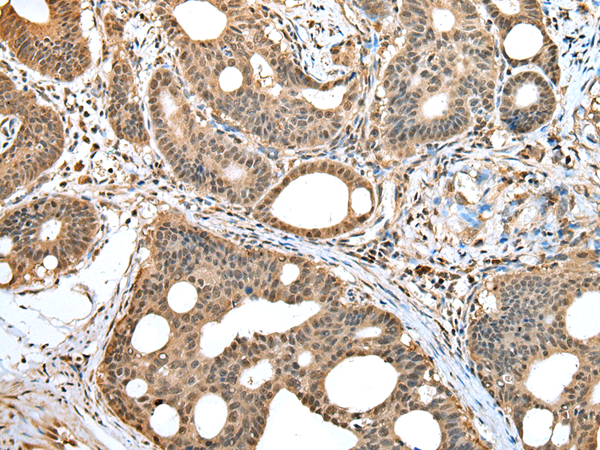

IHC positive control: |

Human gastric cancer and human tonsil |

IHC Recommend dilution: |

25-100 |